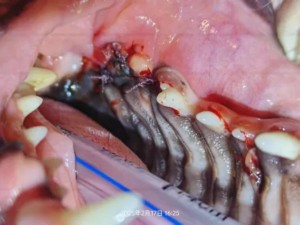

手术治疗照片